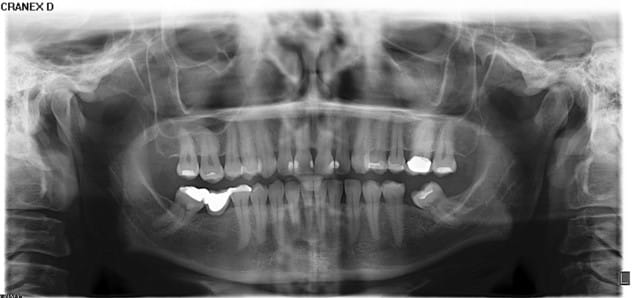

j'ai un patient qui vient en consultation pour ce que je croyait n'être qu'une simple mylolyse. douleur lors du brossage, petits chocs éléctriques, ...mais aussi douleur avec le sucre (inhabituel pour les mylolyses).

en regardant, je ne vois rien,et pas de mylolyse.

je fais une radio, et là.! voici ce qu'on trouve; une jolie cavité dans laquelle la sonde pénètre bien facilement.

Si ça se trouve, ce n'est pas une carie, mais une résorption externe. Il est possible qu'elle communique avec la pulpe, donc, on connaît la suite.

Le pb n'est pas de savoir avec quoi restaurer, le pb est d'abord d'apprécier l'étendue de la lésion et d'en tirer les conséquences.

D57, toi qui sait si bien manier le bistouri, je suis étonné que tu t'interroges sur cette histoire. Si tu fais une légère ostéoplastie (c'est possible car la furcation semble assez loin), en même temps que la gingivectomie, la cicatrisation se fera sous niveau de la lésion. Et la restauration sera au pire, juxta-gingivale. C'est bien ce qu'on recherche, il me semble ?